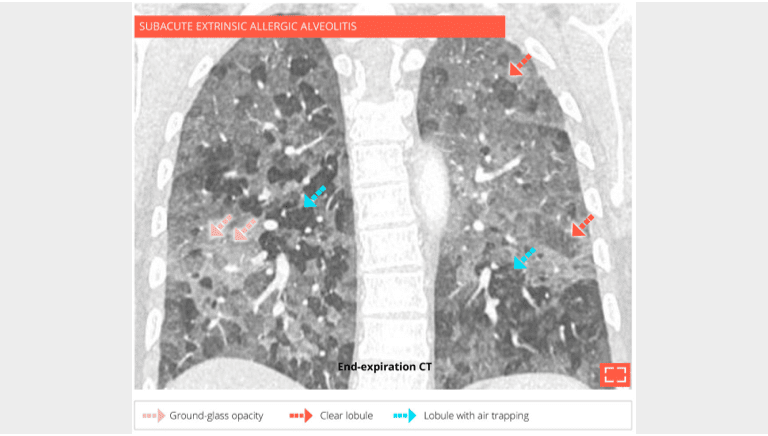

6. Head cheese sign of pulmonary mosaic attenuation

Head cheese sign of pulmonary mosaic attenuation